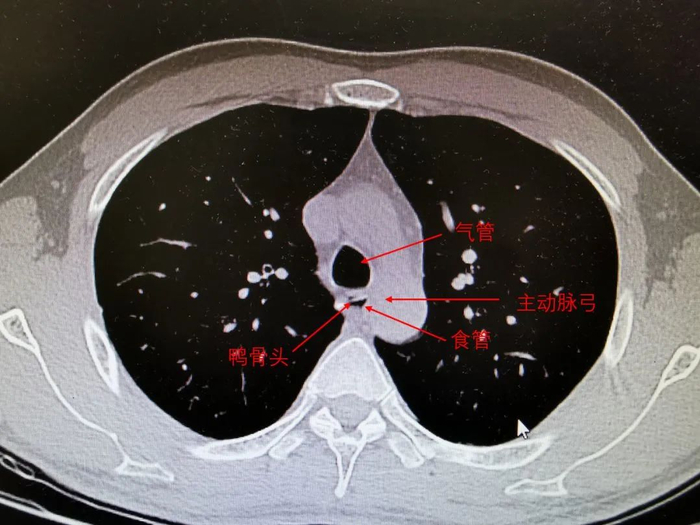

不一会,消化内科协理就来了,点开了 CT,换成了肺窗,肺窗很薄,一层一层看,我站在后面,跟着一起看。

「老师,老师,是这个不是,我指着屏幕上一个高密度的阴影。」

我的胸部CT(带注解)

老师不置可否地点点头。

我兴奋地叫道:「你看,我说吧,肯定有的。」仿佛被洗刷了冤屈。

我还不忘跟老婆装,「老婆,你看,这是主动脉弓,这是肺,这是纵隔。」我卖弄着自己为数不多的专业知识。

我又看了一眼,我的鸭骨头离主动脉弓只有一墙之隔,大概只有 3 毫米,一旦穿破主动脉,引起大出血,那我就凉了。